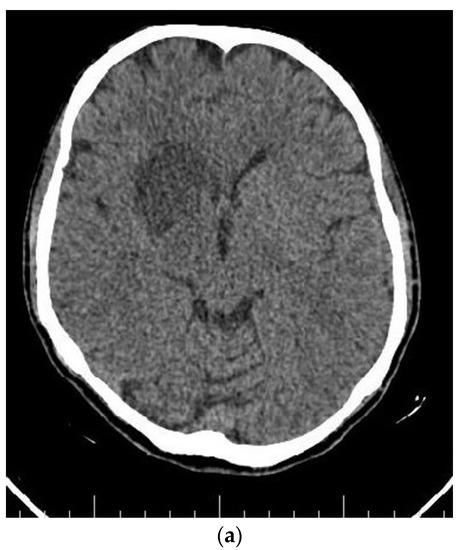

At the end of the radiotherapy period, the patient suffered from a sudden monoparesis of the left upper limb. The CT scan indicated a hypodense lesion in the head of the caudate nucleus, putamen, and anterior thalamus, which was hyperintense in the T1- and T2-weighted MRI. In the MRA, the right internal carotid artery was not visible (Figure 4 and Figure 5). The patient also complained of dyspnea. The patient then underwent a cardiac MRI, which showed multiple masses in the left atrium spreading to the right upper pulmonary vein without obstruction. The patient had a history of open-heart surgery 5 years ago due to a heart mass, which was reported to be fibroma. According to the MRI and history, these lesions have been reported in favor of fibroma.

Figure 4.

Axial (a) CT scan and MRI (b) and MR angiography (c) showing total occlusion of the right carotid artery along with a lesion in basal ganglia.